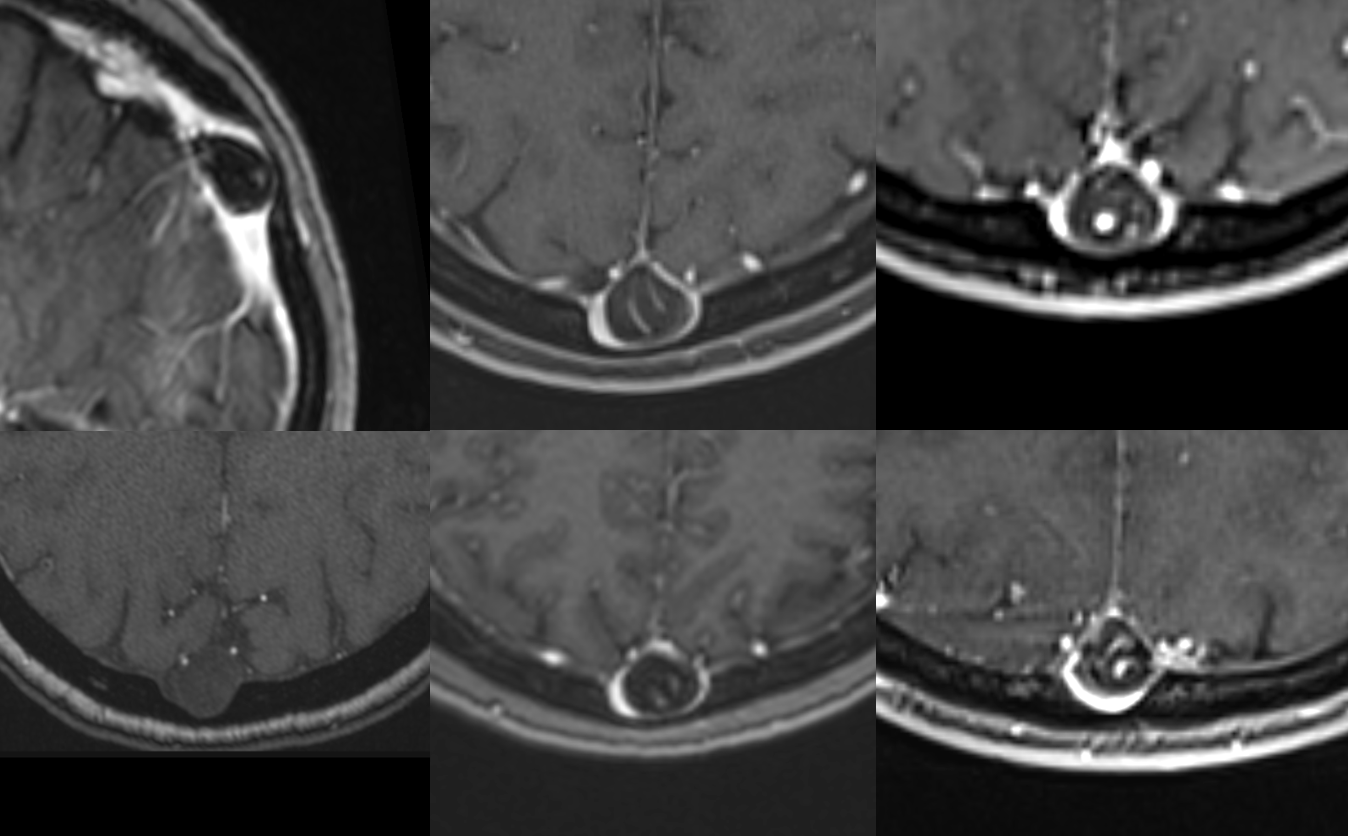

Below is a case of severe venous sinus thrombosis and secondary parenchymal venous infarcts

The explanation for the above tragic pattern is below. On the right, sigmoid and transverse sinuses are patent. However, the Labbe is hypoplastic, and majority of outflow used to go to the Trolard, into the now occluded SSS. There is no other effective way to go — the trolard tries to decompress via a left diploic vein, and convexity tries to access the deep venous system (which normally should not be well-seen in setting of hypoplastic right A1 segment). The left situation is much better, as well-developed superficial sylvian veins drain into the patent Cavernous Sinus. Thus, despite thrombosis of the left transverse and sigmoid sinuses, the left hemisphere is doing better, while the right one, which has patent transverse and sigmoid sinuses, is devastated.

Post venous thrombectomy — with limited results. Note presence of same left diploic vein as seen in right ICA injection, and connection between the distal superior sagittal sinus and the deep venous system via the inferior sagittal sinus.